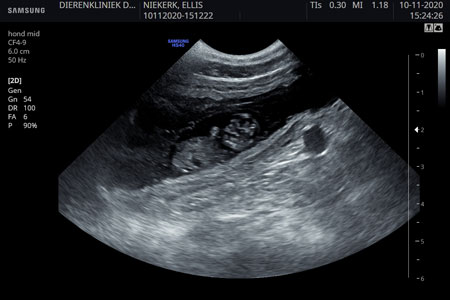

| 10-11-2020 | Ellis is drachtig !! Op de echo waren 8 puppies te zien.![]() |